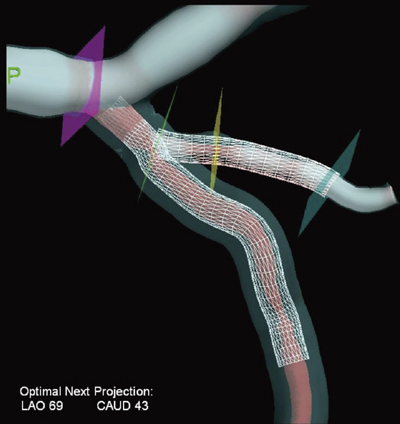

2.CV-3Dデバイス留置計画支援ツール

PCIで使用するデバイスの径,長さに加えて,複数のデバイスを留置する場合に相互の位置関係をあらかじめ把握しておくことは,再狭窄を防止する上で重要である。本ツールは,3D血管像上に仮想デバイスをグラフィックで重ね合わせ表示することで,最適なデバイス選択と留置位置の決定を行い,より安全で,より効率的に手技を実施するための計画作業を支援する。長い領域での狭窄や分岐血管部での複雑な狭窄病変のケースで,PCI経験の浅い術者に対する有用な支援ツールとしても活用できる。図4に,デバイスの仮想表示を用いて,分岐血管における2番目のデバイス留置位置を計画する例を示す。

図4 CV-3Dによるデバイスの仮想表示